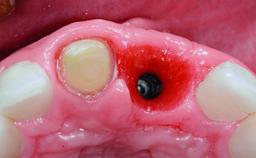

Replacement of a Compromised Upper Right Central Incisor: Hard- and Soft-tissue Augmentation, Late Placement of an RC Bone Level Implant

A 36-year-old male patient with a compromised maxillary central incisor was referred by his general dentist for consultation. The patient’s chief complaints were the gradual debonding of a temporary crown on the right central incisor and unsatisfactory esthetics due to an increasing diastema between the right central and lateral incisors. The patient reported a traumatic event some years previously, when a crown had been placed after root-canal treatment. The referring dentist wanted to provide a new crown restoration, but was concerned about the condition of the residual root. Anamnesis was negative for any other dental or periodontal pathology in the remaining dentition. The patient reported taking no medications: He was a smoker (10 to 15 cigs/day) and had realistic esthetic expectations.